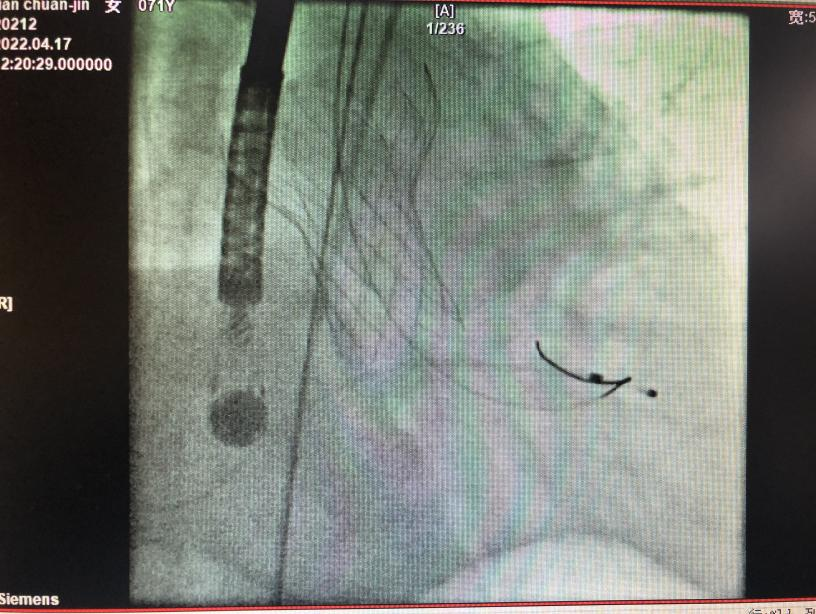

▲TAVR介入手术过程

在多学科的协助下,心内科唐峰博士诊疗团队历经2个多小时,顺利为患者完成经导管主动脉瓣置换术(TAVR)。术后田阿姨恢复良好,顺利出院,她激动的说到“走路不累了,哪里都好了,没想到不开胸也能捡回一条命!”